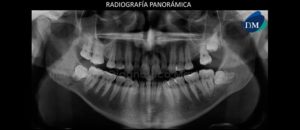

Paciente femenino de 34 años es referido al Instituto de Diagnóstico Maxilofacial para seguimiento de lesión en mandíbula. Se muestra la radiografía panorámica inicial (Figura